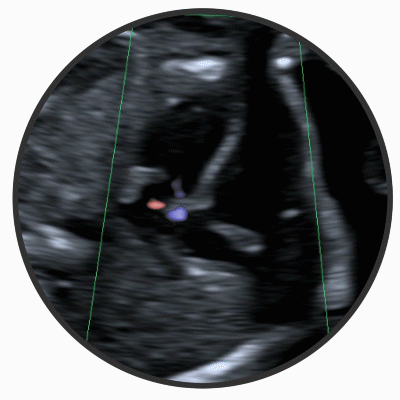

ECHOKARDIOGRAPHIE

In dieser Untersuchung geht es um den Aufbau und die Funktion des kindlichen Herzens.

So können durch die Darstellung der anatomischen Strukturen die meisten schwerwiegenden Herzfehler bereits vor der Geburt entdeckt werden.

Die Auswahl des Entbindungsortes, z.B. eines spezialisierten Krankenhauses mit angeschlossener Kinderklinik kann damit frühzeitig geplant werden. Sollten in Ihrer Familie bereits angeborene Herzfehler aufgetreten sein, kann durch dieses spezielle Verfahren das Herz Ihres Kindes beurteilt werden.